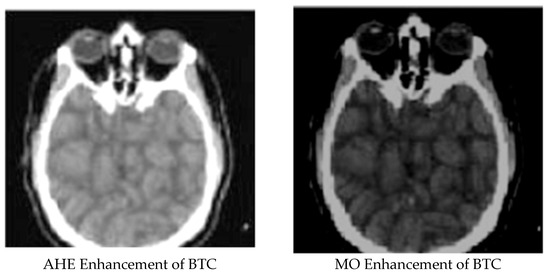

Enhanced and Compressed Output

| 6 | Block truncation compressed image | 0.087685188 | 0.66648485 | 47.63287631 |

| 7 | AHE enhancement for block truncation image | 0.819149803 | 0.001717444 | 75.77798049 |

| 8 | MO enhancement for block truncation image | 0.832122574 | 0.002987536 | 69.33196602 |